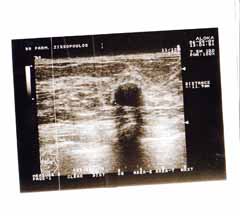

Η κλινικο-υπερηχογραφική διερεύνηση του μαστού είναι μία ακίνδυνη και πολύ αποτελεσματική μέθοδος εντόπισης εστιακών ευρημάτων.

Οι απεικονίσεις των περιστατικών που επιδεικνύονται παρακάτω, έγιναν με κυρτές κεφαλές 3,5 και 5 ΜΗΖ, προκειμένου να φανεί, ότι και με τον εξοπλισμό αυτό, που σιγά-σιγά διαθέτουν όλο και περισσότερα ιατρεία, είμαστε σε θέση να έχουμε ικανοποιητικά αποτελέσματα.

Oι τελευταίες 4 απεικονίσεις έγιναν με ειδικό για μαστό ηχοβολέα linear, εναλλασσομένης συχνότητος 7,5-10ΜΗΖ.